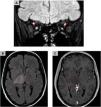

The aim of this work is to provide a diagnostic approach to the potential causes of optic neuropathy, focusing on the radiological findings associated with this pathology. Various etiologies have been identified, including inflammatory and demyelinating optic neuritis, developmental and hereditary diseases, neurodegenerative disorders, infectious conditions, post-traumatic causes, ischemic optic neuropathy (with anterior ischemic optic neuropathy being the most common form), and neoplastic etiologies. Optical coherence tomography and magnetic resonance imaging play a fundamental role in the diagnosis of optic neuropathy, allowing to distinguish patterns of optic nerve involvement. These studies are essential to locate and characterize the different pathologies, increasing the precision of the diagnosis in diseases presenting optic neuropathy as the main symptom. In conclusion, the findings obtained from magnetic resonance imaging are essential in the differential diagnosis of optic nerve diseases, aiding in the localization and characterization of various pathologies affecting either the optic pathway alone or multiple levels of the central nervous system and thereby increasing diagnostic accuracy.